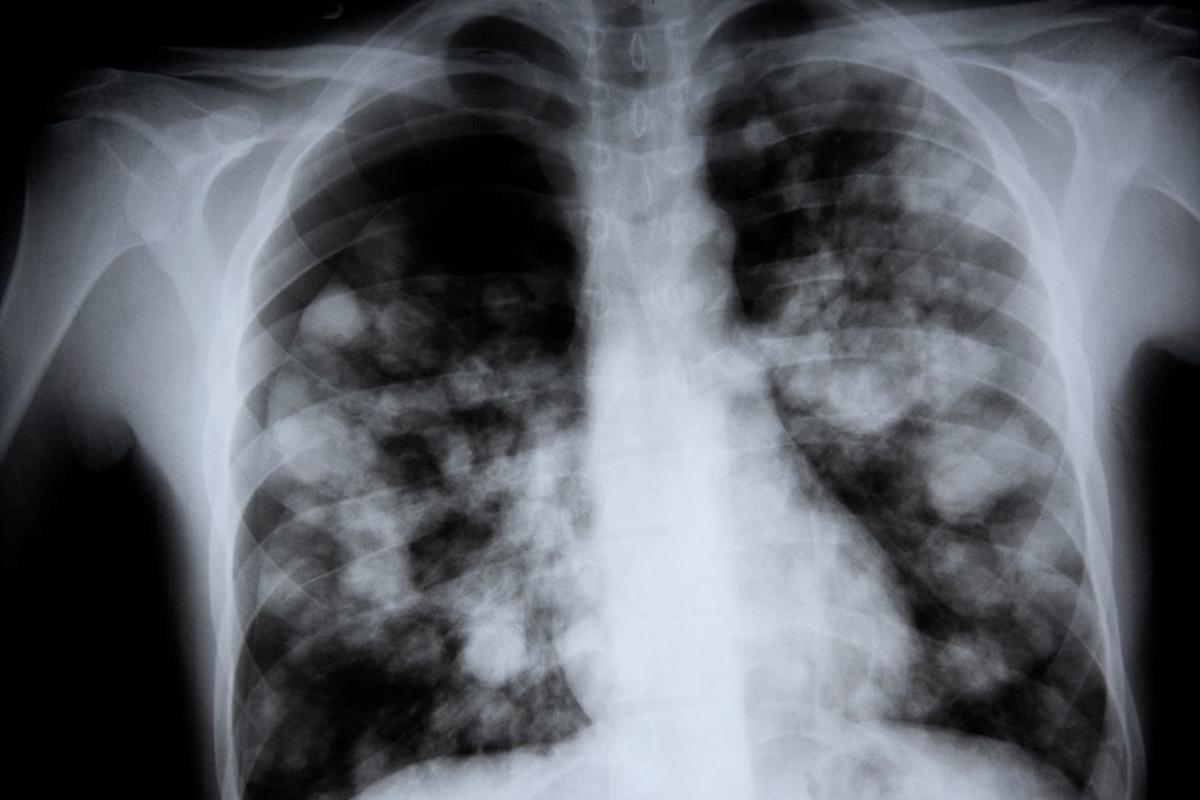

- Chest X-rays to check if pneumonia has gone away.